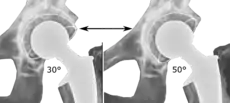

The direction of the acetabular cup influences the range of motion of the leg, and also affects the risk of dislocation.[9] For this purpose, the acetabular inclination and the acetabular anteversion are measurements of cup angulation in the coronal plane and the sagittal plane, respectively.